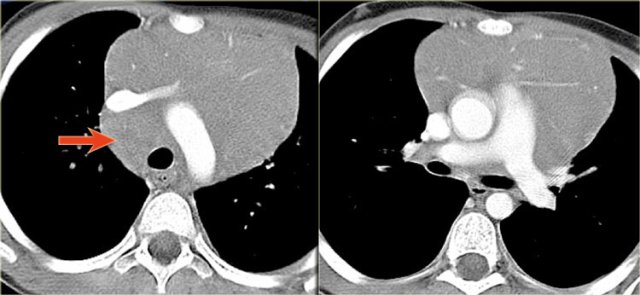

LEFT: Thymoma. RIGHT: Thymic carcinoma. LEFT: Thymoma. RIGHT: Thymic carcinoma.

Thymoma

Thymomas are common and account for 20% of mediastinal neoplasms.

Thymic carcinomas are extremely rare and acount for less than 1% of all thymic tumors.

The images show a thymoma on the left and a carcinoma on the right.

The thymic carcinoma has invaded the superior vena cava (arrow).